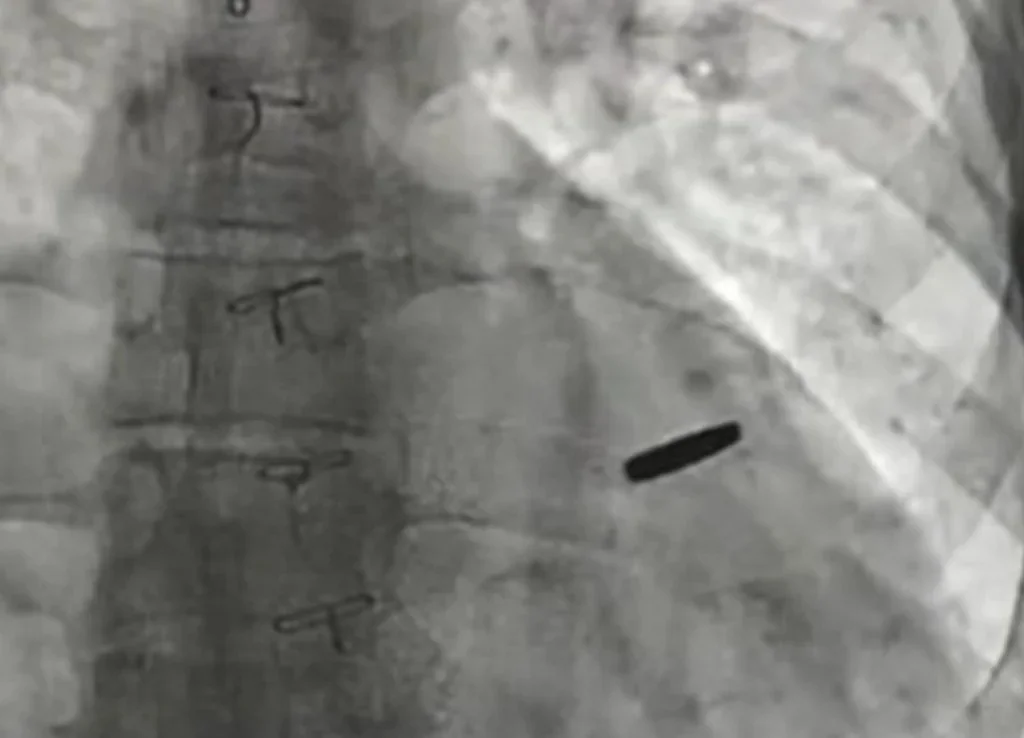

З серця звільненого з російського полону українського військового дістали кулю, з якою він прожив три роки.

«Три роки він був з цієї кулею, прожив. На щастя, вона нічого не пошкодила, зараз ми її видалили, пощастило хлопцю», — наголосив Тодуров.